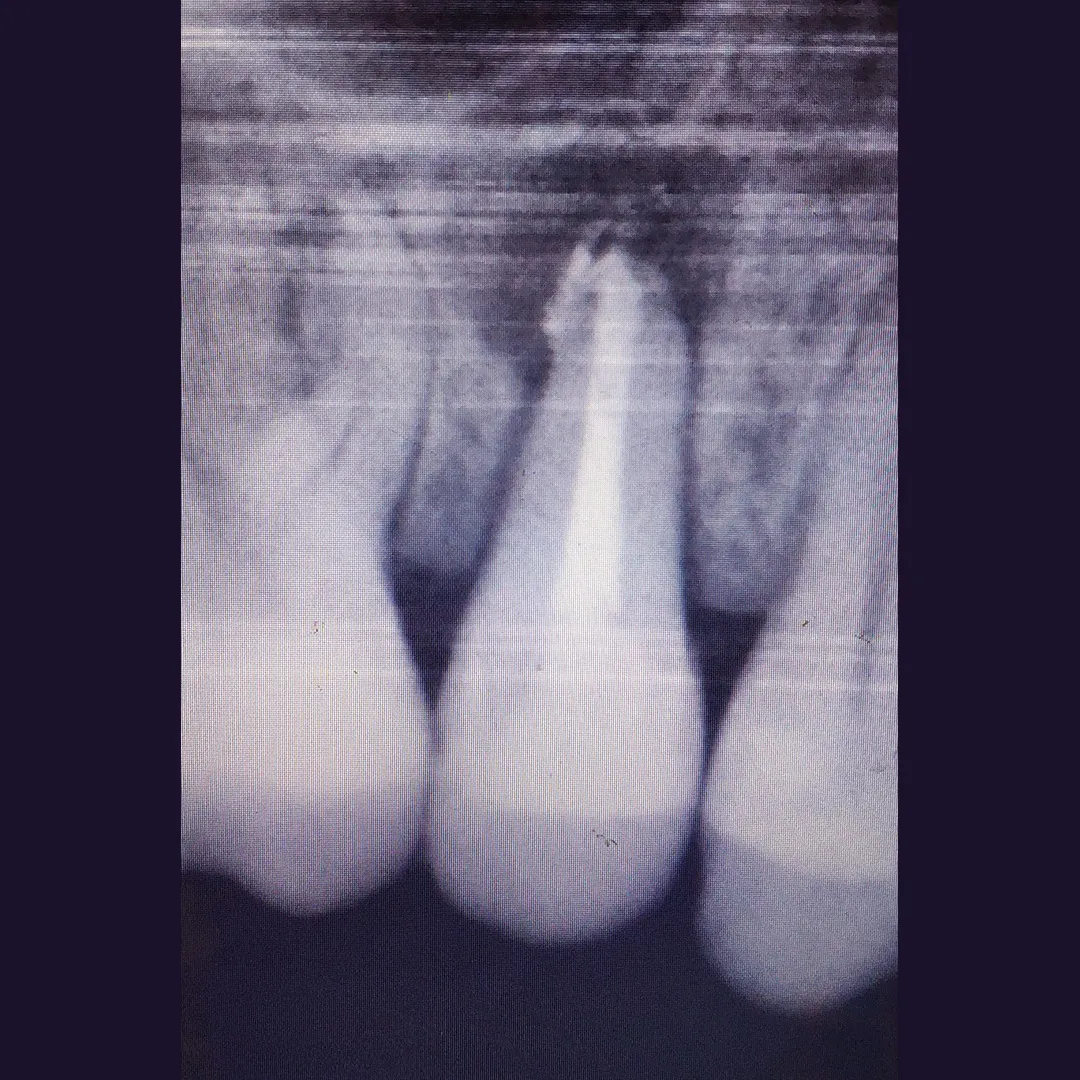

Эндодонтическое лечение верхнего резца в результате обострения хронического пульпита зуба 1.2Смотреть работуСрок лечения:90 минутСумма лечения:8 600 руб.